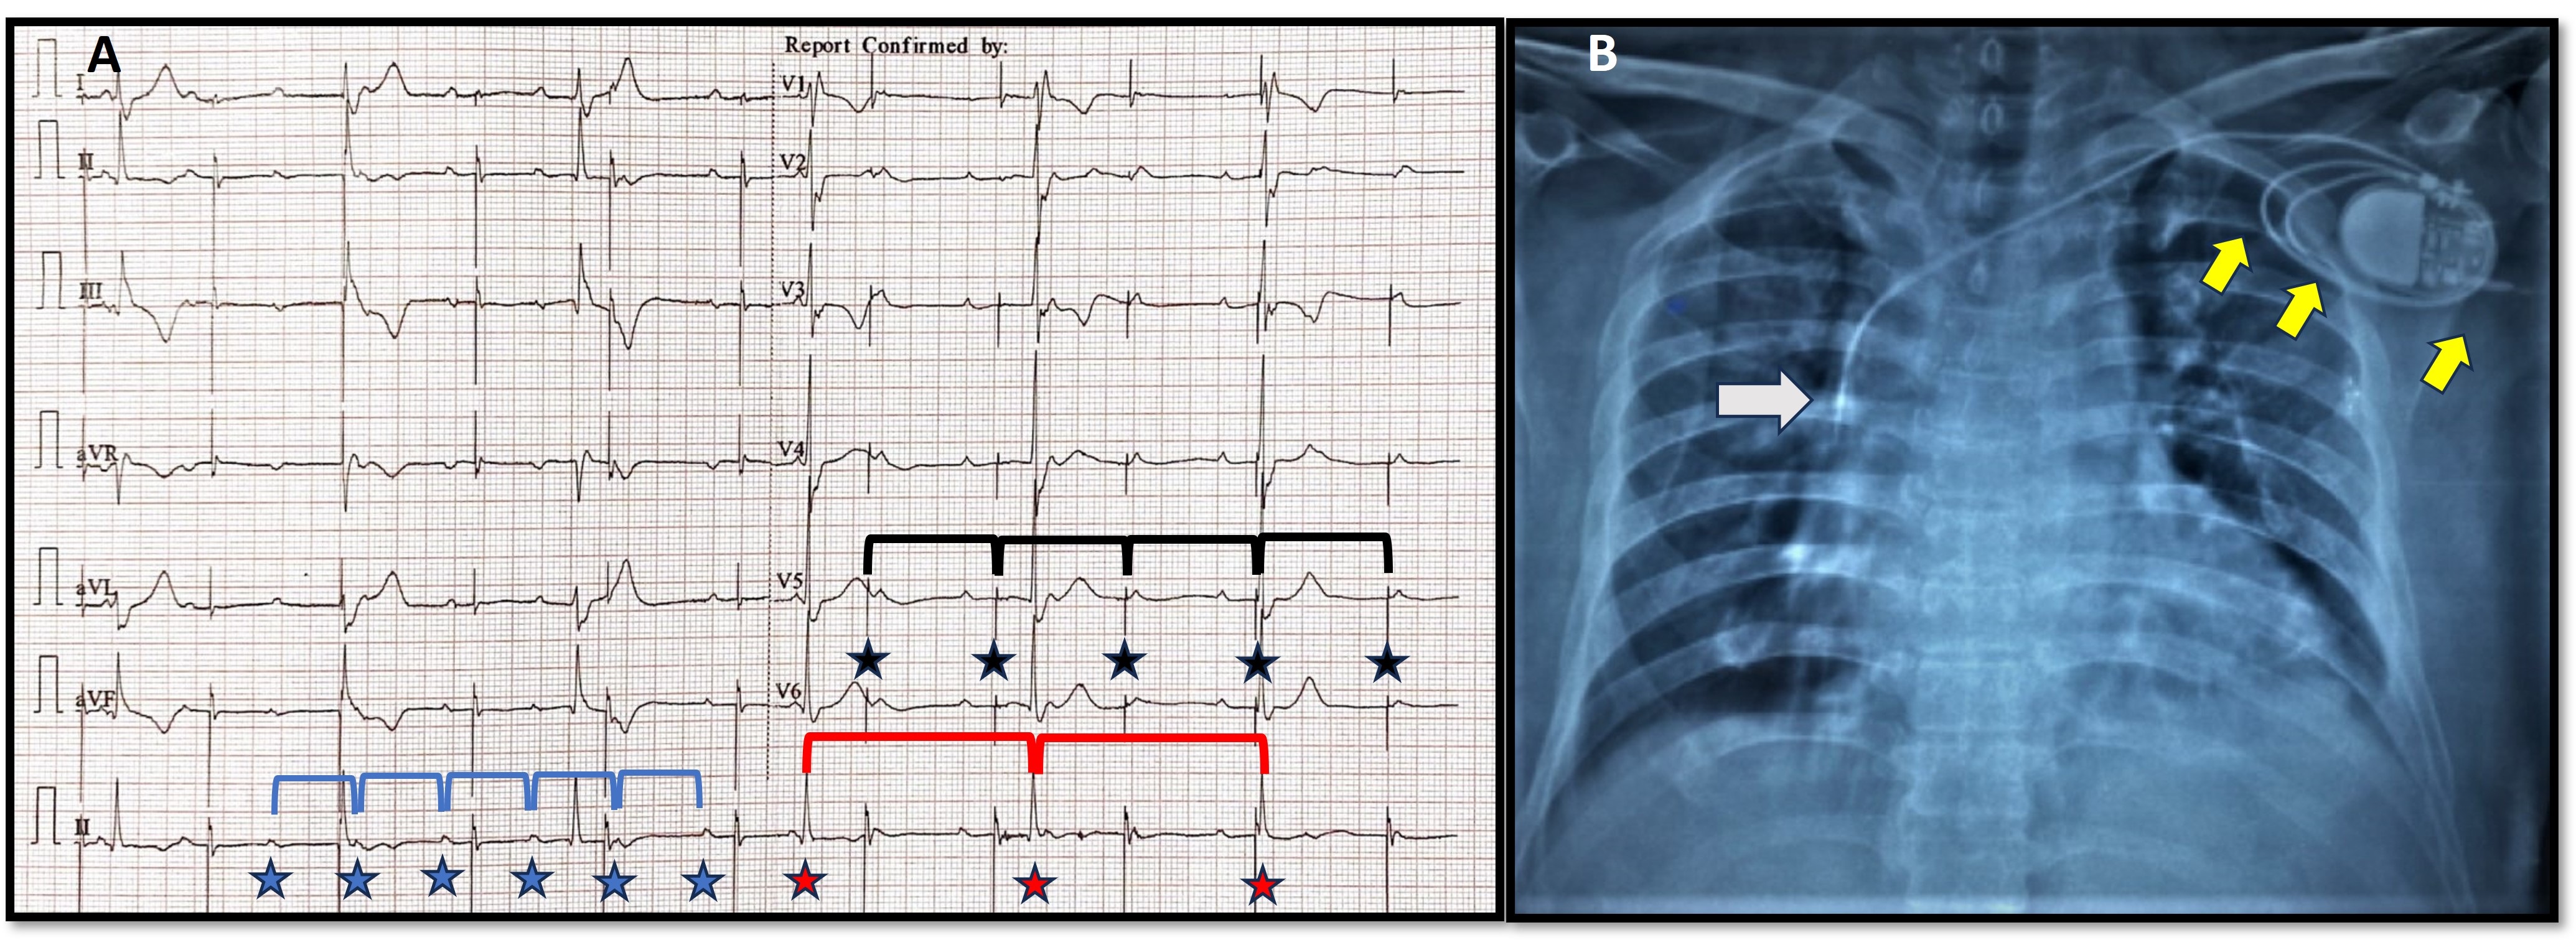

ECG analysis (Figure 2A) showed baseline atrioventricular (AV) dissociation with an atrial rate of 100 bpm. Pacemaker stimulus artifact was noted at regular intervals of 66/min (lower set rate of the VVIR pacemaker) but was not followed by a P wave or QRS complex (capture failure). Intrinsic ventricular escape rhythm was wide (QRS duration 0.16 sec) at a rate of 36 bpm and was not sensed (sensing failure). Chest X-ray (Figure 2B) revealed macro-dislodgement of ventricular lead with tip placed along the superior vena cava-right atrial (SVC-RA) junction, and coiling of leads around the pacemaker generator in its spacious pocket. No obvious lead fracture or insulation breaks were evident. The pacemaker pocket was reopened, and leads were uncoiled, repositioned, and connected to the same generator. Reduction of pocket size to snugly fit the pulse generator, tight suture sleeve fixation of the lead, and extra reinforcement suture fixation of the generator to the pectoral muscle were done.